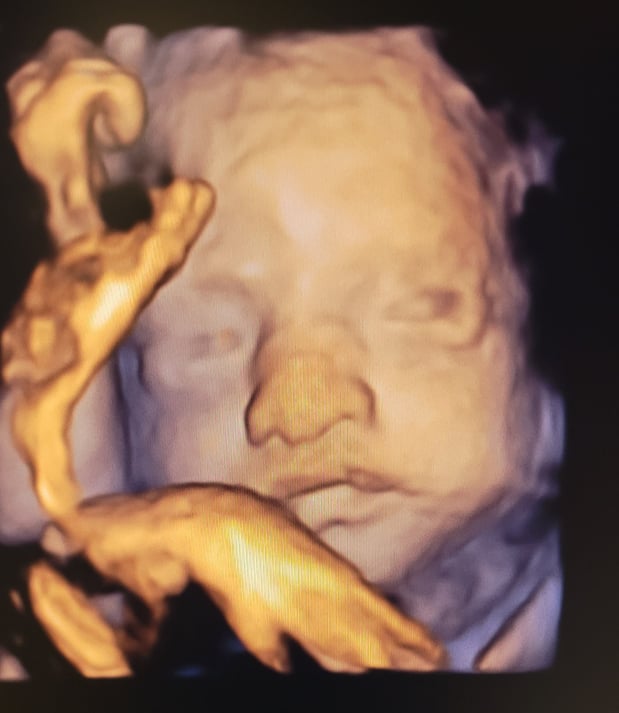

Tasha Crump, is registered by the American Registry of Diagnostic Medical Sonographers (ARDMS) and have over 18 years experience in medical diagnostic sonography specializing in Maternal Fetal Medicine. She is a highly proficient in the art of 3D 4D ultrasound. Tasha has practiced and trained in NYC's top ranked hospitals including Columbia Presbyterian. At Love at First Sight Imaging Studio you'll be in a very comfortable and calming atmosphere for you and your family to bond with your baby. We have state of the art equipment with HD Live to image unbelievably realistic views of your baby. You will fall in Love at First Sight.